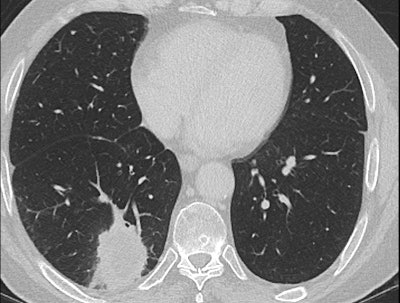

In her Liverpool talk, Strickland showed examples of missed lung cancers. In one case, leading to a duty of candour procedure, the lung bases, visible on a CT scan of the abdomen performed for suspected pancreatic pathology, had not been looked at on lung contrast windows, causing a small right basal lung cancer to be missed (see images above). On a subsequent chest CT scan several months later, the lesion was much bigger, and a second cancer was present in the left upper lobe. A duty of candour was issued because the lung cancer was at a higher stage when it was finally detected, likely leading to a worse outcome for the patient.

As we discussed in consultation this morning, I am very sorry that your CT scan undertaken to investigate pain in your abdomen and pancreas on Xth April 2014 did, in fact, show a small nodule in the bottom of the right lung. It is likely this was the early stage of the squamous cell cancer that we have now found in the right lung and are planning to treat.

A full and thorough investigation will be carried out by XXX Hospital as to why this small nodule was overlooked on the CT scan and why the scan was not flagged to the lung cancer team.